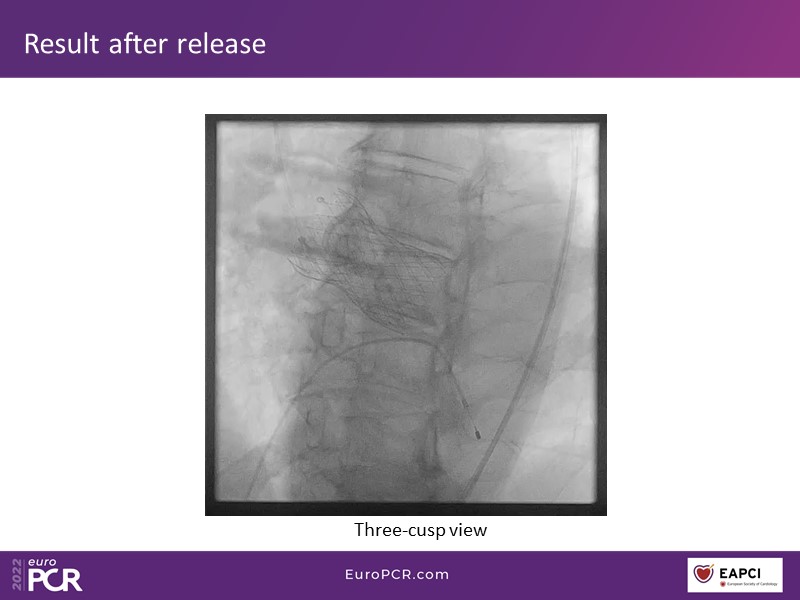

How to deal with challenging anatomies? Find answers in this EuroPCR 2022 session with case studies to explore and learn how to achieve optimal patient outcomes with Evolut platform, uncover practical tips and techniques to achieve implant precision and control, and become familiar with technical considerations and procedural execution of TAVI.